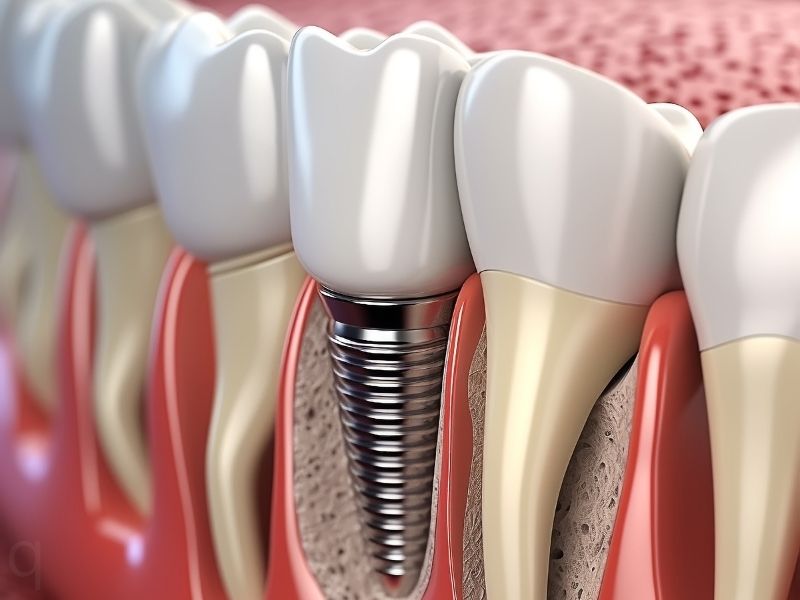

What Are Dental Implants?

A dental implant is an artificial titanium root placed in your jawbone to replace missing teeth.

It supports a crown, bridge, or denture, giving you a fixed and permanent replacement that feels completely natural.

Dental Implant Procedure at Smile Makers

Implant Placement

A titanium screw is gently placed into the jawbone under local anesthesia. -

Healing & Integration

The implant fuses with your bone (osseointegration) in 2–3 months. -

Final Crown Placement

A natural-looking crown is attached, completing your permanent new tooth.